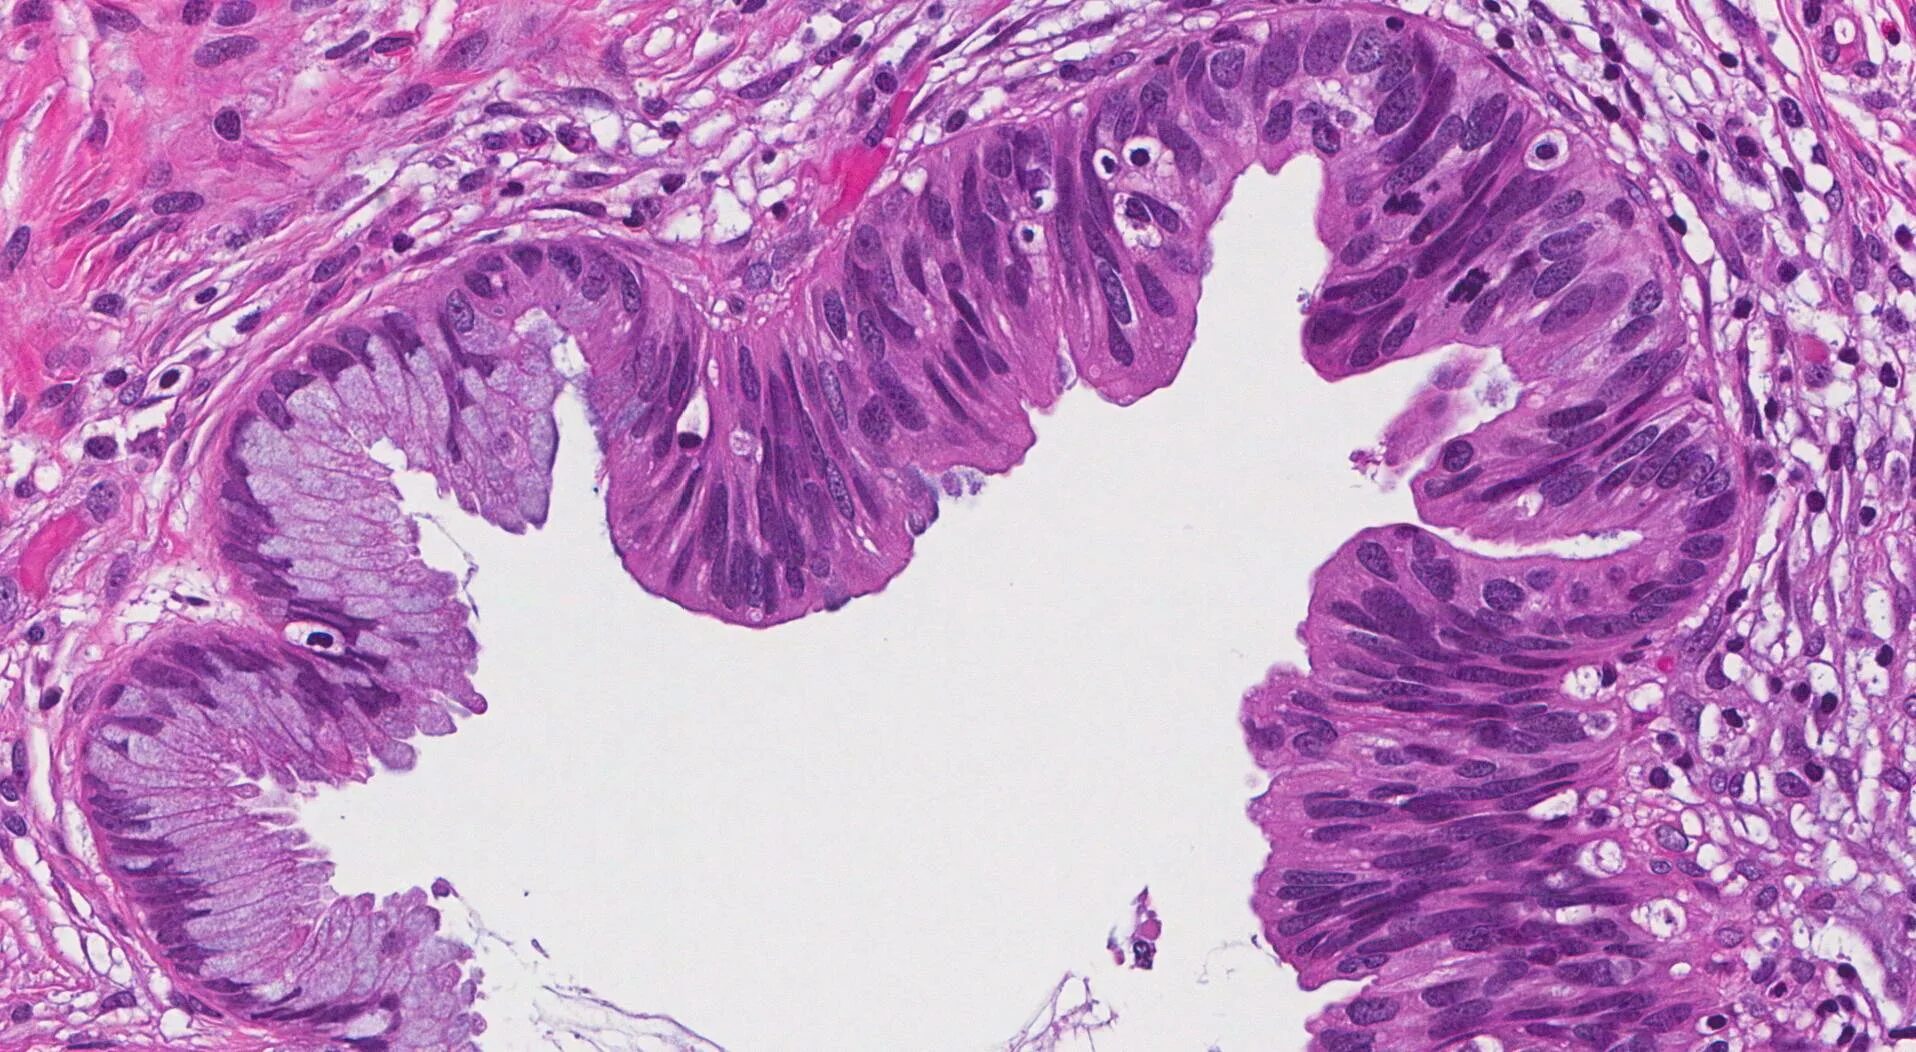

Гистологическое исследование полипа